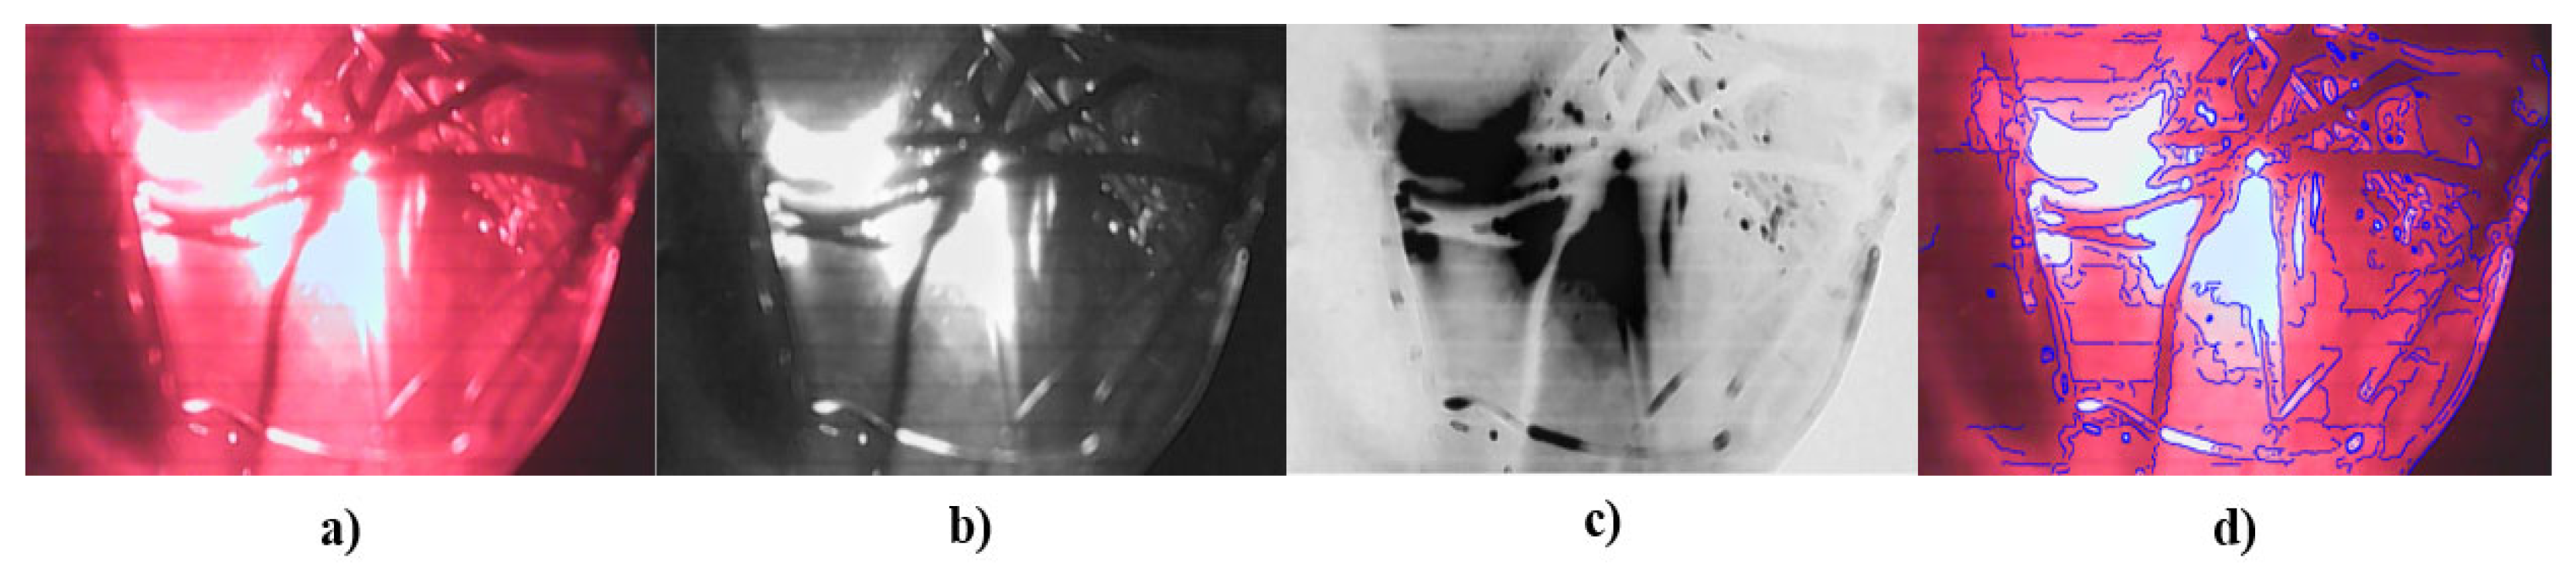

The image processing algorithm consists of three distinct stages. First, the green channel of the image is selected, which helps to contrast the vascularity inside the tissue due to the optical properties of hemoglobin. This technique is known as “red-free” [47,48,49]. The second stage consists of obtaining the inverse of the green channel to segment the contours. Finally, the third stage contrasts the contours in the image with the original capture. Figure 12 shows a block diagram of the algorithm used to process the digital images.

A test with the prosthesis that simulates tumors was carried out by processing the image in MATLAB® to identify the area of abnormality and to subsequently perform a segmentation of the area of interest, as shown in Figure 13. After the tests on the tumor phantom, the same process was carried out for the veins and blood vessel phantom. This information is shown in Figure 14.

In the phantom tumor images, the contrast between the contour image with the original image, as in Figure 13d, is not clearly observed; i.e., the abnormalities detected by the system are not completely segmented. This occurs because the camera detects the reflection from the light source. This phenomenon does not represent a drawback, because it is totally dependent on the phantom’s material, whereas, in in vivo studies, the images will only depend on breast density and the patient’s skin color.

In Figure 13d and Figure 14d, the transmitted light of the irradiation source can be appreciated, but, in Figure 13d, the segmentation of the findings inside the phantom shows better results. This is because the reflection is not close to the interest area.

It is possible to distinguish the different elements inside the phantom (tumors or vascularity), but, due to lighting, it detects the transmitted light of the source as noise because of the contrast between the background and the objects of interest; therefore, when the algorithm identifies the contours, the transmitted light is also detected. Considering that the goal of the developed DOM system is to provide visual reference information that allows specialists to give or complement a diagnosis, we decided to show, as additional information, the image that represents the inverse of the green channel, where the tumors or vascularity inside the phantom are displayed in a similar way as in conventional mammography.

Figure 13. Results from tumor phantom: (a) original image, (b) green channel of the image, (c) inverse of green channel, and (d) contrast between contour image detection and original image.

Figure 14. Results from blood vessel phantom: (a) original image, (b) green channel of the image, (c) inverse of green channel, and (d) contrast between contour image detection and original image.